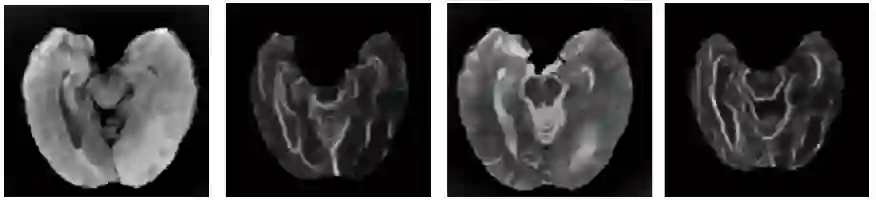

Cross modal image syntheses is gaining significant interests for its ability to estimate target images of a different modality from a given set of source images,like estimating MR to MR, MR to CT, CT to PET etc, without the need for an actual acquisition.Though they show potential for applications in radiation therapy planning,image super resolution, atlas construction, image segmentation etc.The synthesis results are not as accurate as the actual acquisition.In this paper,we address the problem of multi modal image synthesis by proposing a fully convolutional deep learning architecture called the SynNet.We extend the proposed architecture for various input output configurations. And finally, we propose a structure preserving custom loss function for cross-modal image synthesis.We validate the proposed SynNet and its extended framework on BRATS dataset with comparisons against three state-of-the art methods.And the results of the proposed custom loss function is validated against the traditional loss function used by the state-of-the-art methods for cross modal image synthesis.